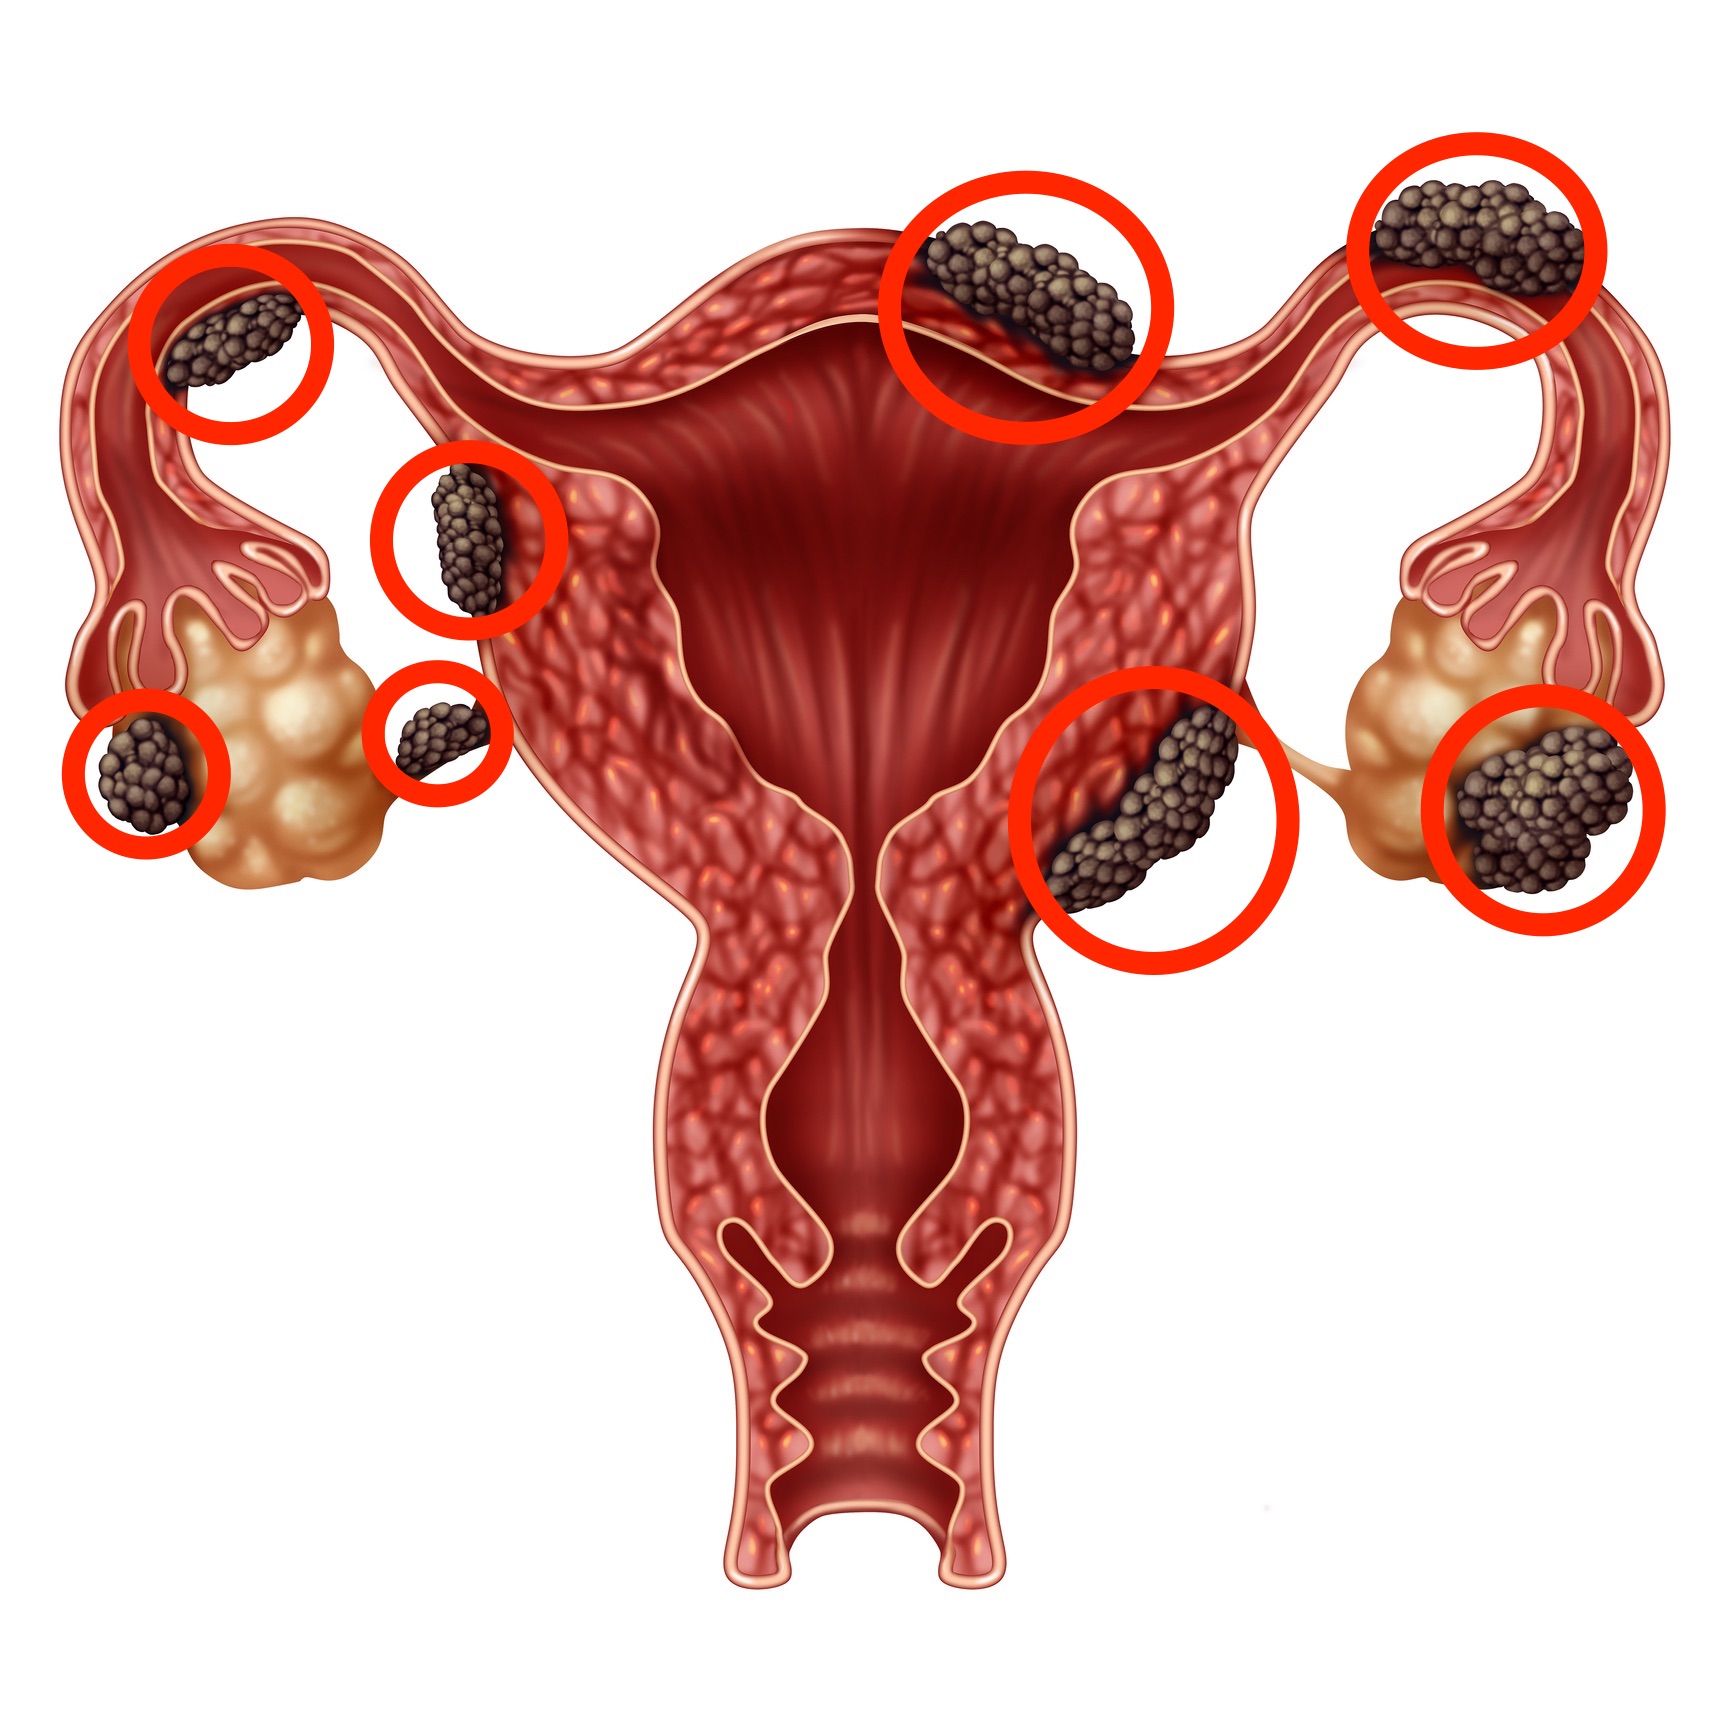

Боль в малом тазу у женщин: Причины и подходы к лечению